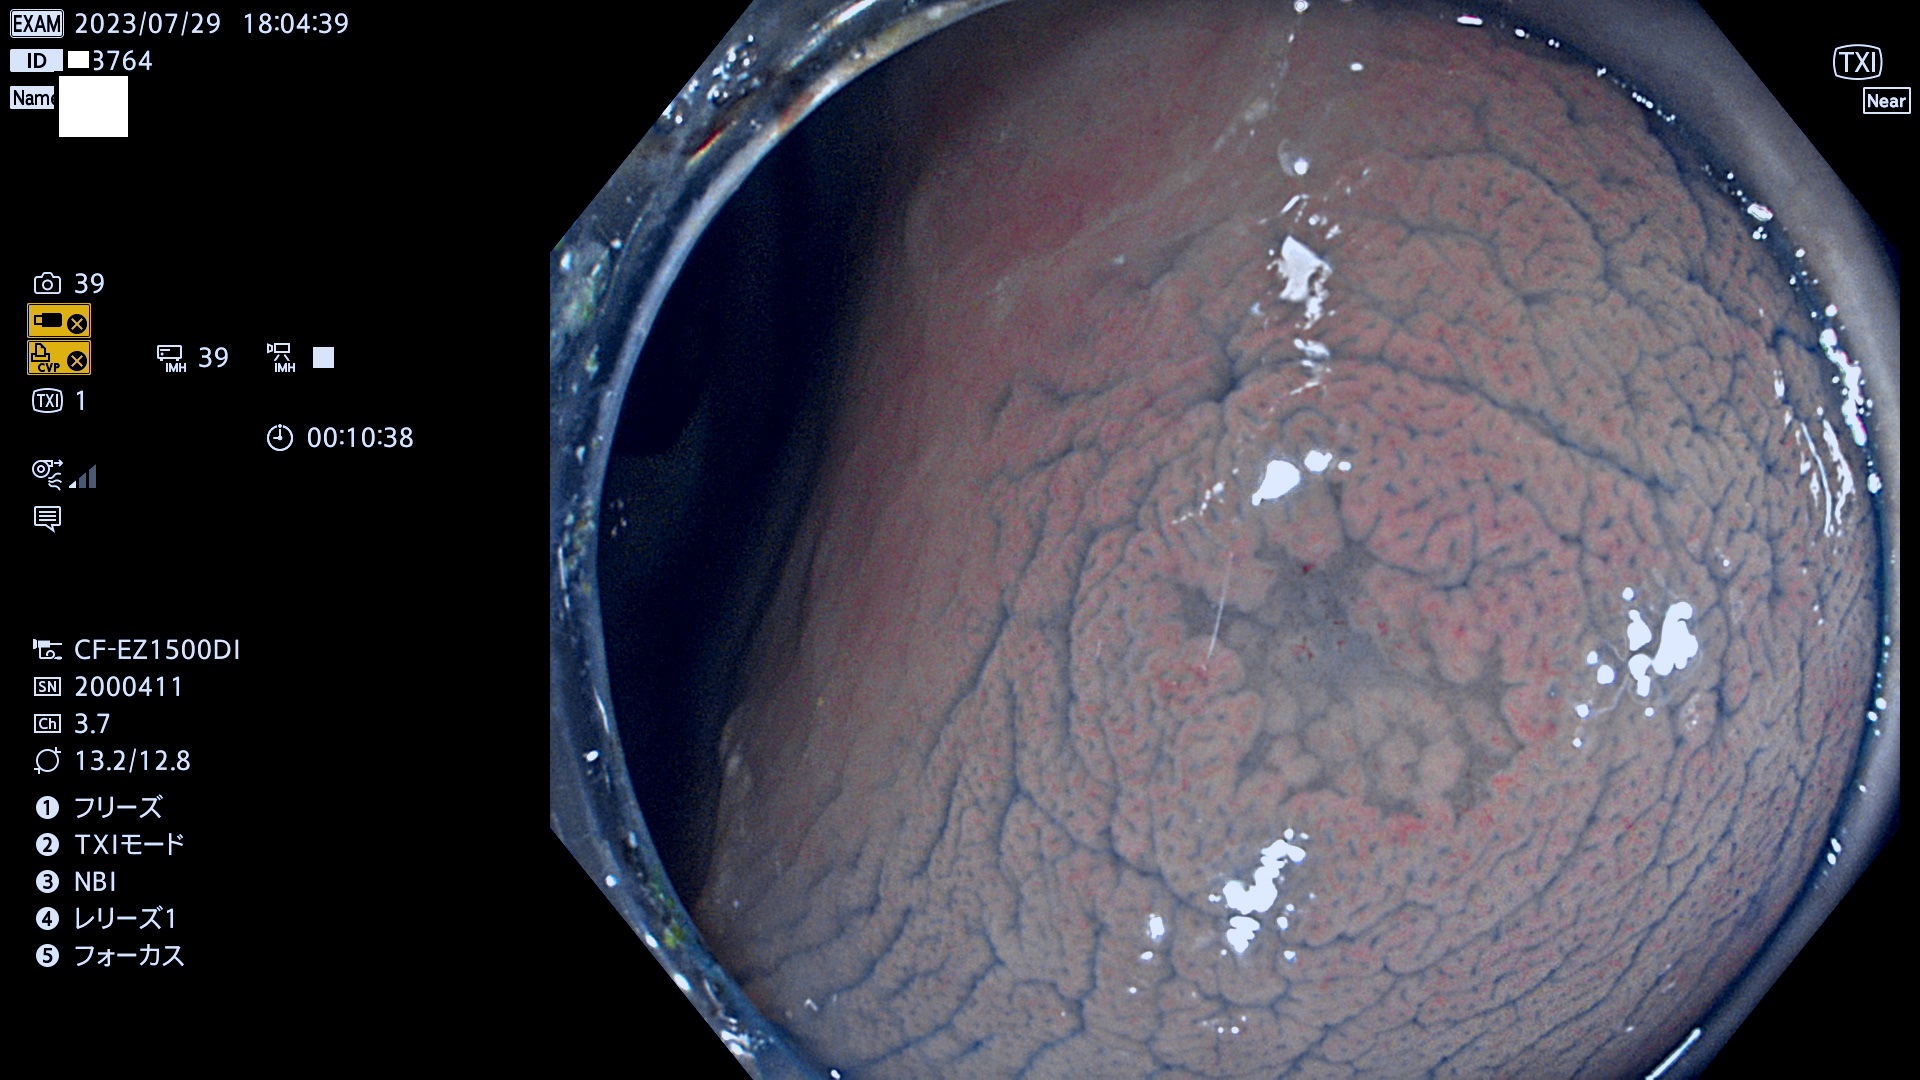

表面型腺腫(Flat Adenoma)の中で、完全に平坦な物をUb、陥凹している物をUcと呼びます。平坦隆起型(Ua)よりも、発見が難しく危険な病変です。このタイプは「内視鏡後・大腸癌の重要犯人」であり、この発見率は「腺腫発見率」よりも、重要な意味があります。

専門的)何故、陥凹していると危険? 癌遺伝子の変異が蓄積すると細胞分裂が盛んになり隆起するのでは?と通常は思われるでしょう。しかし実際は逆です。これは2022年の記事にある「細胞はストレスに直面したら細胞分裂を止める(細胞老化に入り休眠する)という生命の基本的現象」によるものです(Oncogene Stress)。細胞老化を起こすのが癌抑制遺伝子で、この安全装置(ブレーキ)が壊れると癌になります(休眠からの覚醒)。ですから陥凹は「まだ癌では無いが癌化の直前」を意味します。特に「小サイズなのに陥凹している」病変は短期間に腫瘍進化(⇒2021年記事)が起きたことを意味します(=ゲノム不安定性

専門的)Uc=De Novo癌? 内視鏡の解像度が低かった時代、このような説もありました。しかし今日の高精度内視鏡では良性の微小なUc型腺腫が日常的に見つかります。私見ですが「Ucこそが多段階発癌(Adenoma-Carcinoma Sequence)のMain Route」と考えます。

毎週の検査(木・金・土・日)に発見されたUb、Uc型・腺腫を、その週の日曜の夜にUPし1週間、提示します。

抽出の対象期間 2023年7月27日(木)〜7月30(日)の4日間(48件の検査)11件